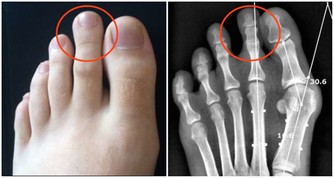

骨質疏鬆症的主要特徵是骨礦物質含量低下、骨強度降低、易發生骨折等。上了年紀的老人家走路駝背、身高降低,其實都是骨質疏鬆症的表現。

與此同時,骨質疏鬆症也被稱為“沉默的殺手”。因骨頭“變脆”,容易導致骨折。

在年齡大於50歲的中老年人群中,女性得骨質疏鬆的機率比男性大得多,且在今後的生活中會發生骨質疏鬆相關的脆性骨折。而骨折後,臥床期間死亡率極高,骨質疏鬆也因此被稱為“老年人最後的喪鐘”。